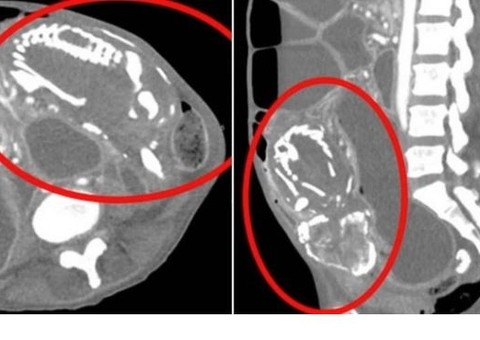

Exames de imagem mostraram que depois de passar pela uretra, o objeto acabou se posicionando na horizontal na bexiga.